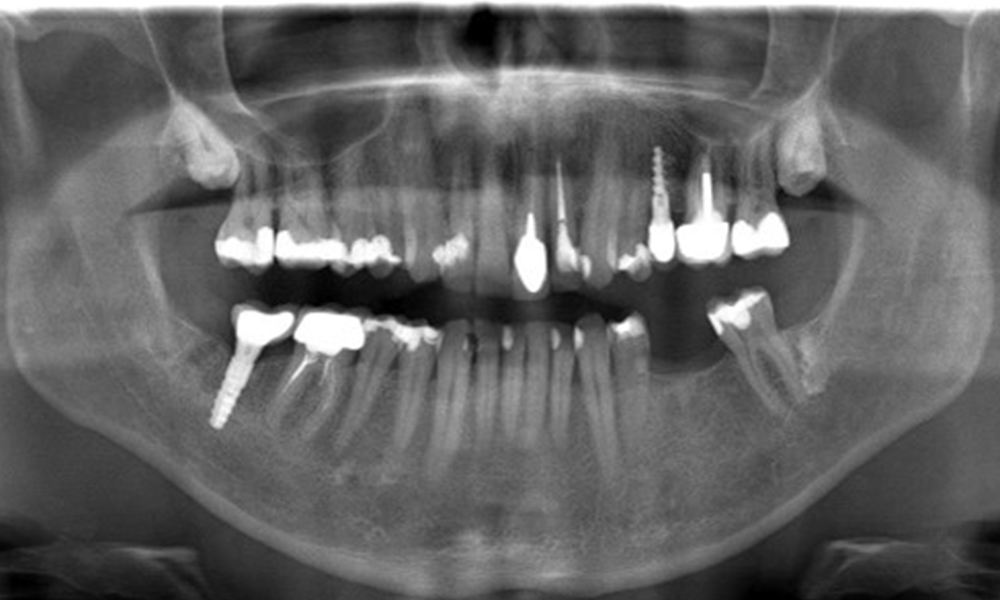

The X-ray image shows the bone loss

The X-ray images show the bone loss.

OPG: 29/02/2024